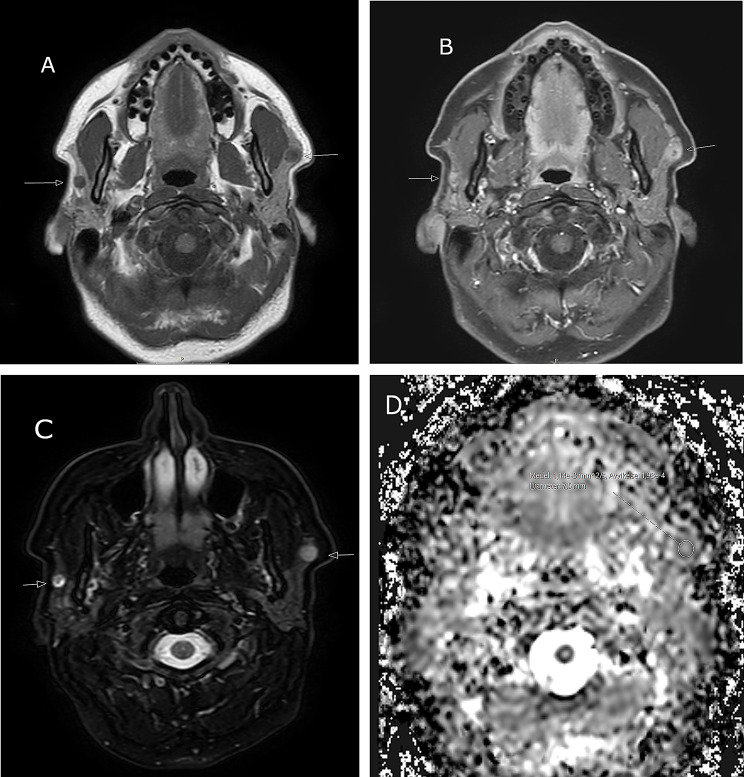

Case presentation: Here three cases of synchronous bilateral salivary gland tumors are described and discussed. Recognizing the entity is important for diagnostics and treatment planning. The first patient was a 56-year-old female with a bilateral parotid tumor, a malignant tumor, salivary duct carcinoma on the right side and a benign tumor, pleomorphic adenoma on the left side. The second patient was a 50-year old female with a bilateral benign parotid tumor, a pleomorphic adenoma. The third patient was a 51-year old female with a bilateral malignant tumor, an acinic cell carcinoma. Details on the diagnostic work-up, histopathology and treatment are described and discussed.

Conclusions: In the case of a unilateral salivary gland tumor, especially of the major glands, the contralateral gland is always included in the clinical and radiological (MRI) head and neck evaluation prior to surgery, to detect or exclude possible bilateral occurrence.